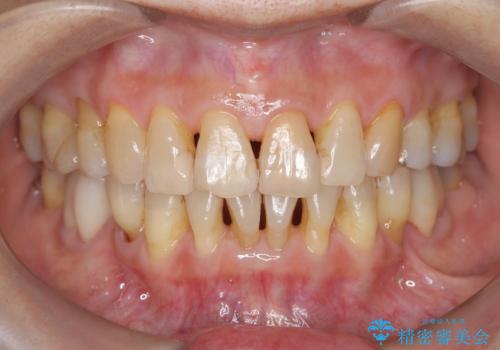

- インビザライン(マウスピース矯正)の治療中にステインが気になり、クリーニング希望とのことでした。

アタッチメントの周囲などに、ステインの付着や、プラークがみられたためPMTC(自費クリーニング)30分コースを行いました。

インビザラインで矯正治療中に、クリーニングを行ったbeforeafter写真です。